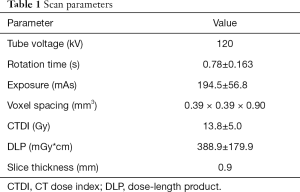

Image acquisition was performed in supine position using a 128-slice MDCT scanner (Ingenuity Core 128; Philips Healthcare, Cleveland, OH). An initial scout scan was used for planning purposes. Then a helical scan was performed with implicit tube current modulation. Scan parameters are shown in Table 1.

Full table